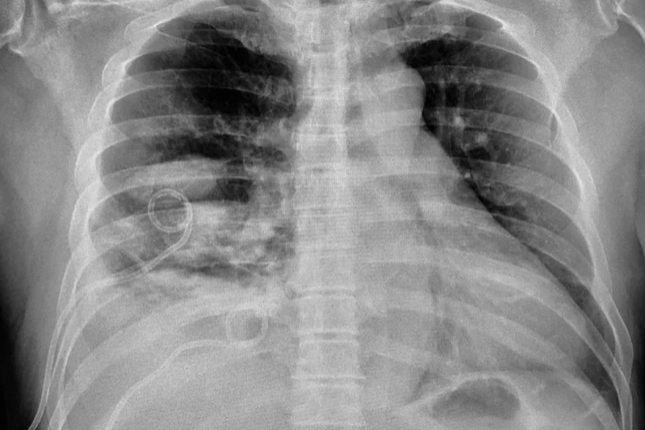

Community acquired pneumonia (CAP)

vs. Pneumocystis jirovecii pneumonia (PCP)

Diffuse bilateral infiltrates

Patchy areas of ground-glass attenuation